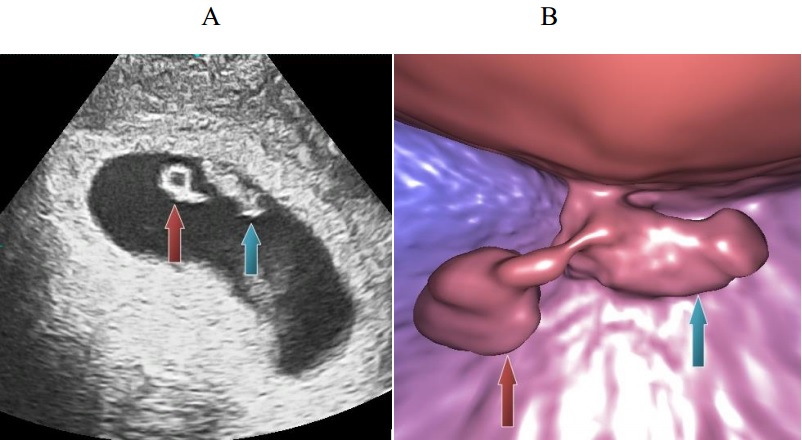

A lo largo de los últimos dos años el equipo del doctor Tesarik ha desarrollado otras nuevas aplicaciones de la endoscopia virtual en ginecología, incluyendo la histerosalpingoscopia virtual, la embrioscopia virtual y la foliculoscopia virtual. La técnica de histerosalpingoscopia virtual fue desarrollada para detectar la presencia del embarazo ectópico con un saco gestacional implantado en una trompa uterina. Por su parte, la embrioscopia virtual, permite visualizar embriones recién implantados en el útero con una resolución superior en comparación con las técnicas utilizadas anteriormente. Finalmente la foliculoscopia virtual facilita la visualización del contenido de los folículos ováricos y la identificación de folículos “vacíos”, que no contienen ningún óvulo.

En otros casos las mujeres estimuladas para la FIV desarrollan muy pocos folículos, algunos de los cuales pueden estar vacíos (sin un óvulo dentro). “La foliculoscopia virtual nos permite detectar los folículos vacíos y interrumpir el tratamiento antes de llegar a la punción ovárica”. Esta información permite la paciente ahorrar el coste de una tentativa de FIV sin esperanza de éxito alguna y no se expone a una intervención quirúrgica inútil. Este ahorro puede servir para repetir la estimulación utilizando procedimientos diferentes a base de la experiencia obtenida durante la tentativa fracasada. “En estos dos años nos hemos encontrado 12 casos similares y en 8 de ellos obtuvimos óvulos en la tentativa repetida.”